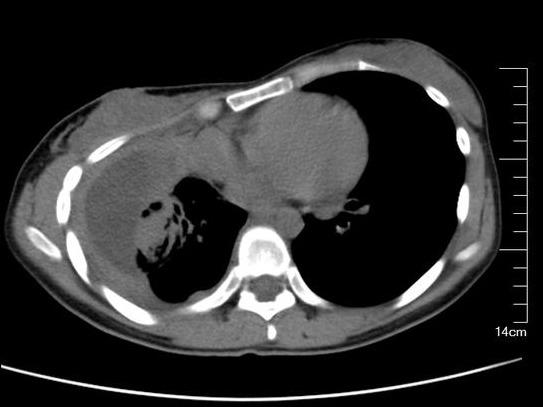

术前胸部CT:右侧胸廓塌陷畸形,肋间隙变窄,包裹性胸腔积液,肺膨胀不良

术前胸部CT纵膈窗左侧胸膜增厚包裹性脓胸